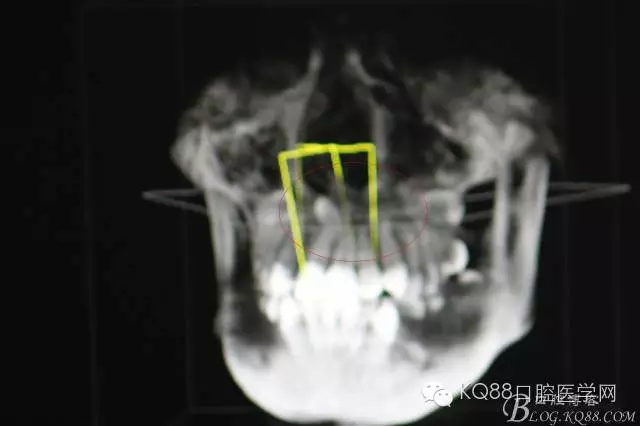

圖4.cbct的三維重建影像:多生牙牙尖幾乎和鼻底相通